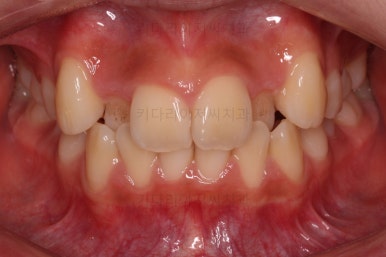

연산동치과 초진 시, 입안의 모습입니다.

보시다시피 앞니쪽이 많이 삐뚤고요. 어금니쪽이 긴밀하지 못한 부정교합이 있네요.

그리고 왼쪽 하단의 사진에 화살표를 보시면, 예전에 신경치료를 해둔 치아인데 어린 나이에 신경치료를 하다보니 크라운으로 치료를 마무리 하지 못했어요.